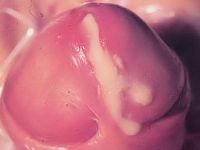

Gonorroe (druiper) Gonorroe (druiper)

gonorroe (druiper) intracellulaire diplococcen

Foto's: CDC - Wikimedia (Public Domain Images).

Indien er intracellulaire diplococcen zichtbaar zijn, en de patiënt heeft klachten, kan direct gestart worden met behandeling voor gonorroe. Omdat 10-50% tevens Chlamydia heeft, komt dat neer op dezelfde combinatie als bij blinde therapie: ceftriaxon 500 mg i.m., in combinatie met azithromycine 1 g ineens, of doxycycline 2 dd 100 mg gedurende 7 dagen. Zie verder onder gonorroe.